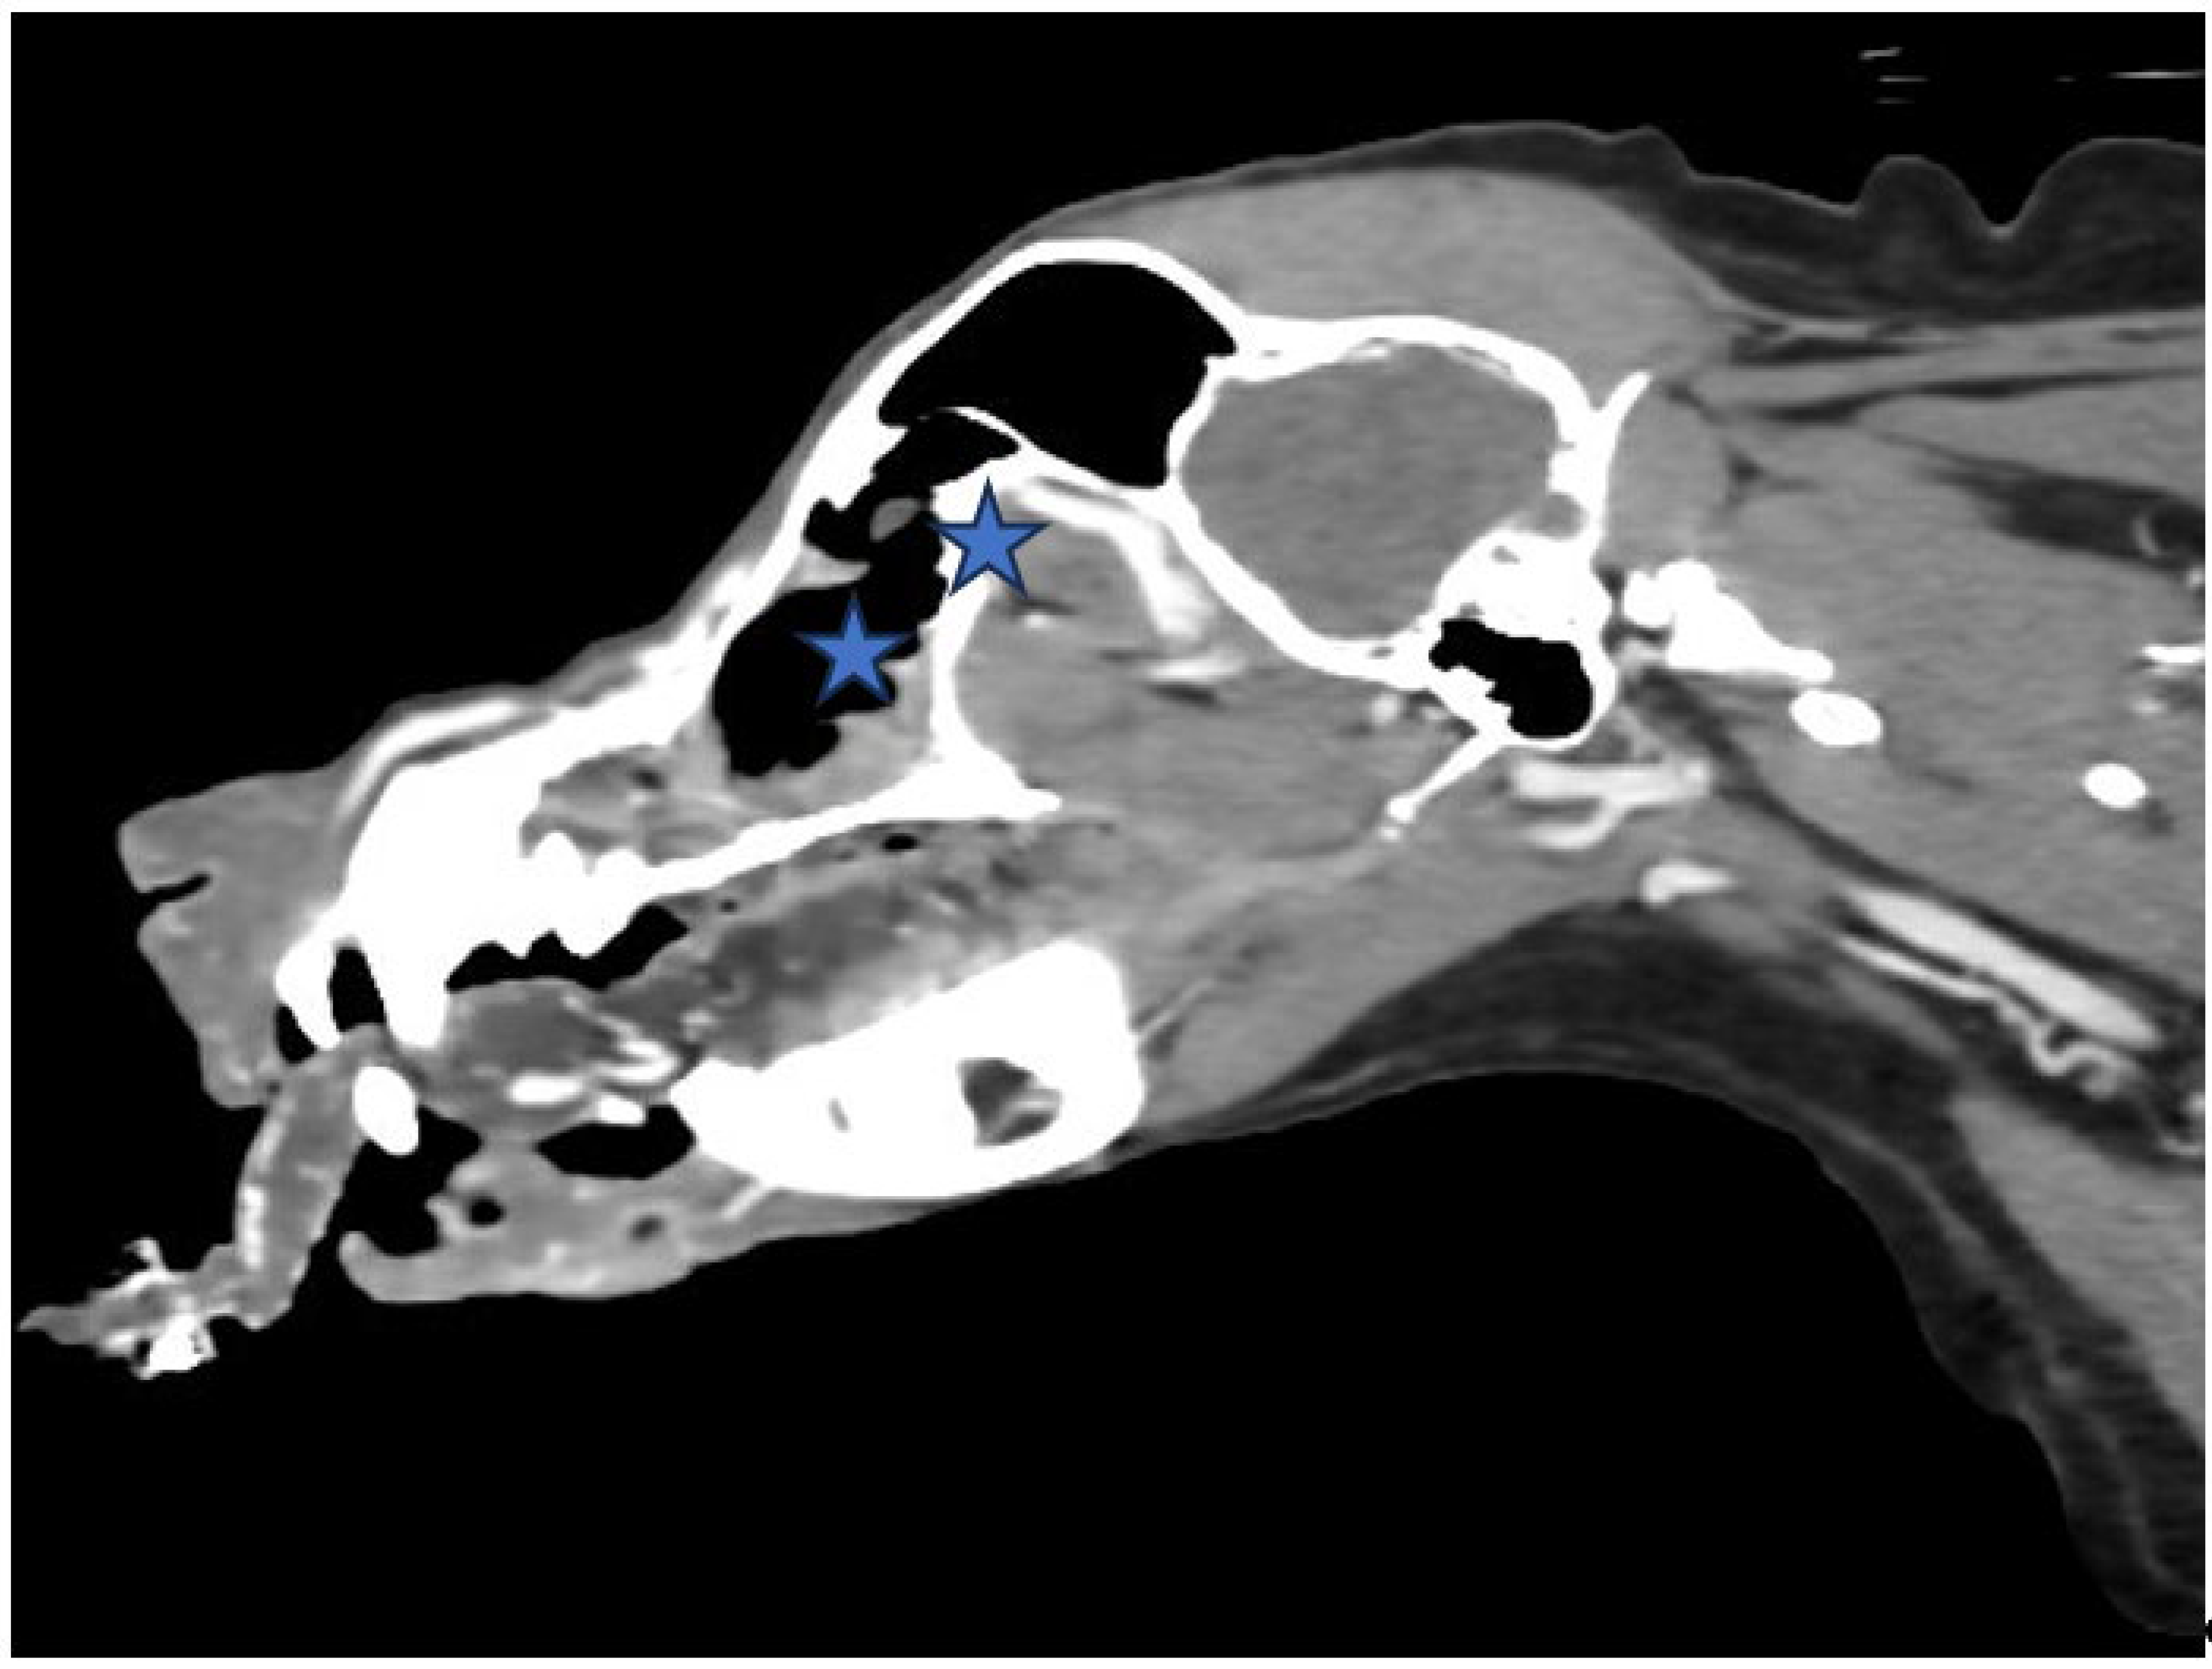

Figure 3. (A,B). Sagittal view of CT scan of skull The size of the nasal tumor decreased significantly (Asteroid).